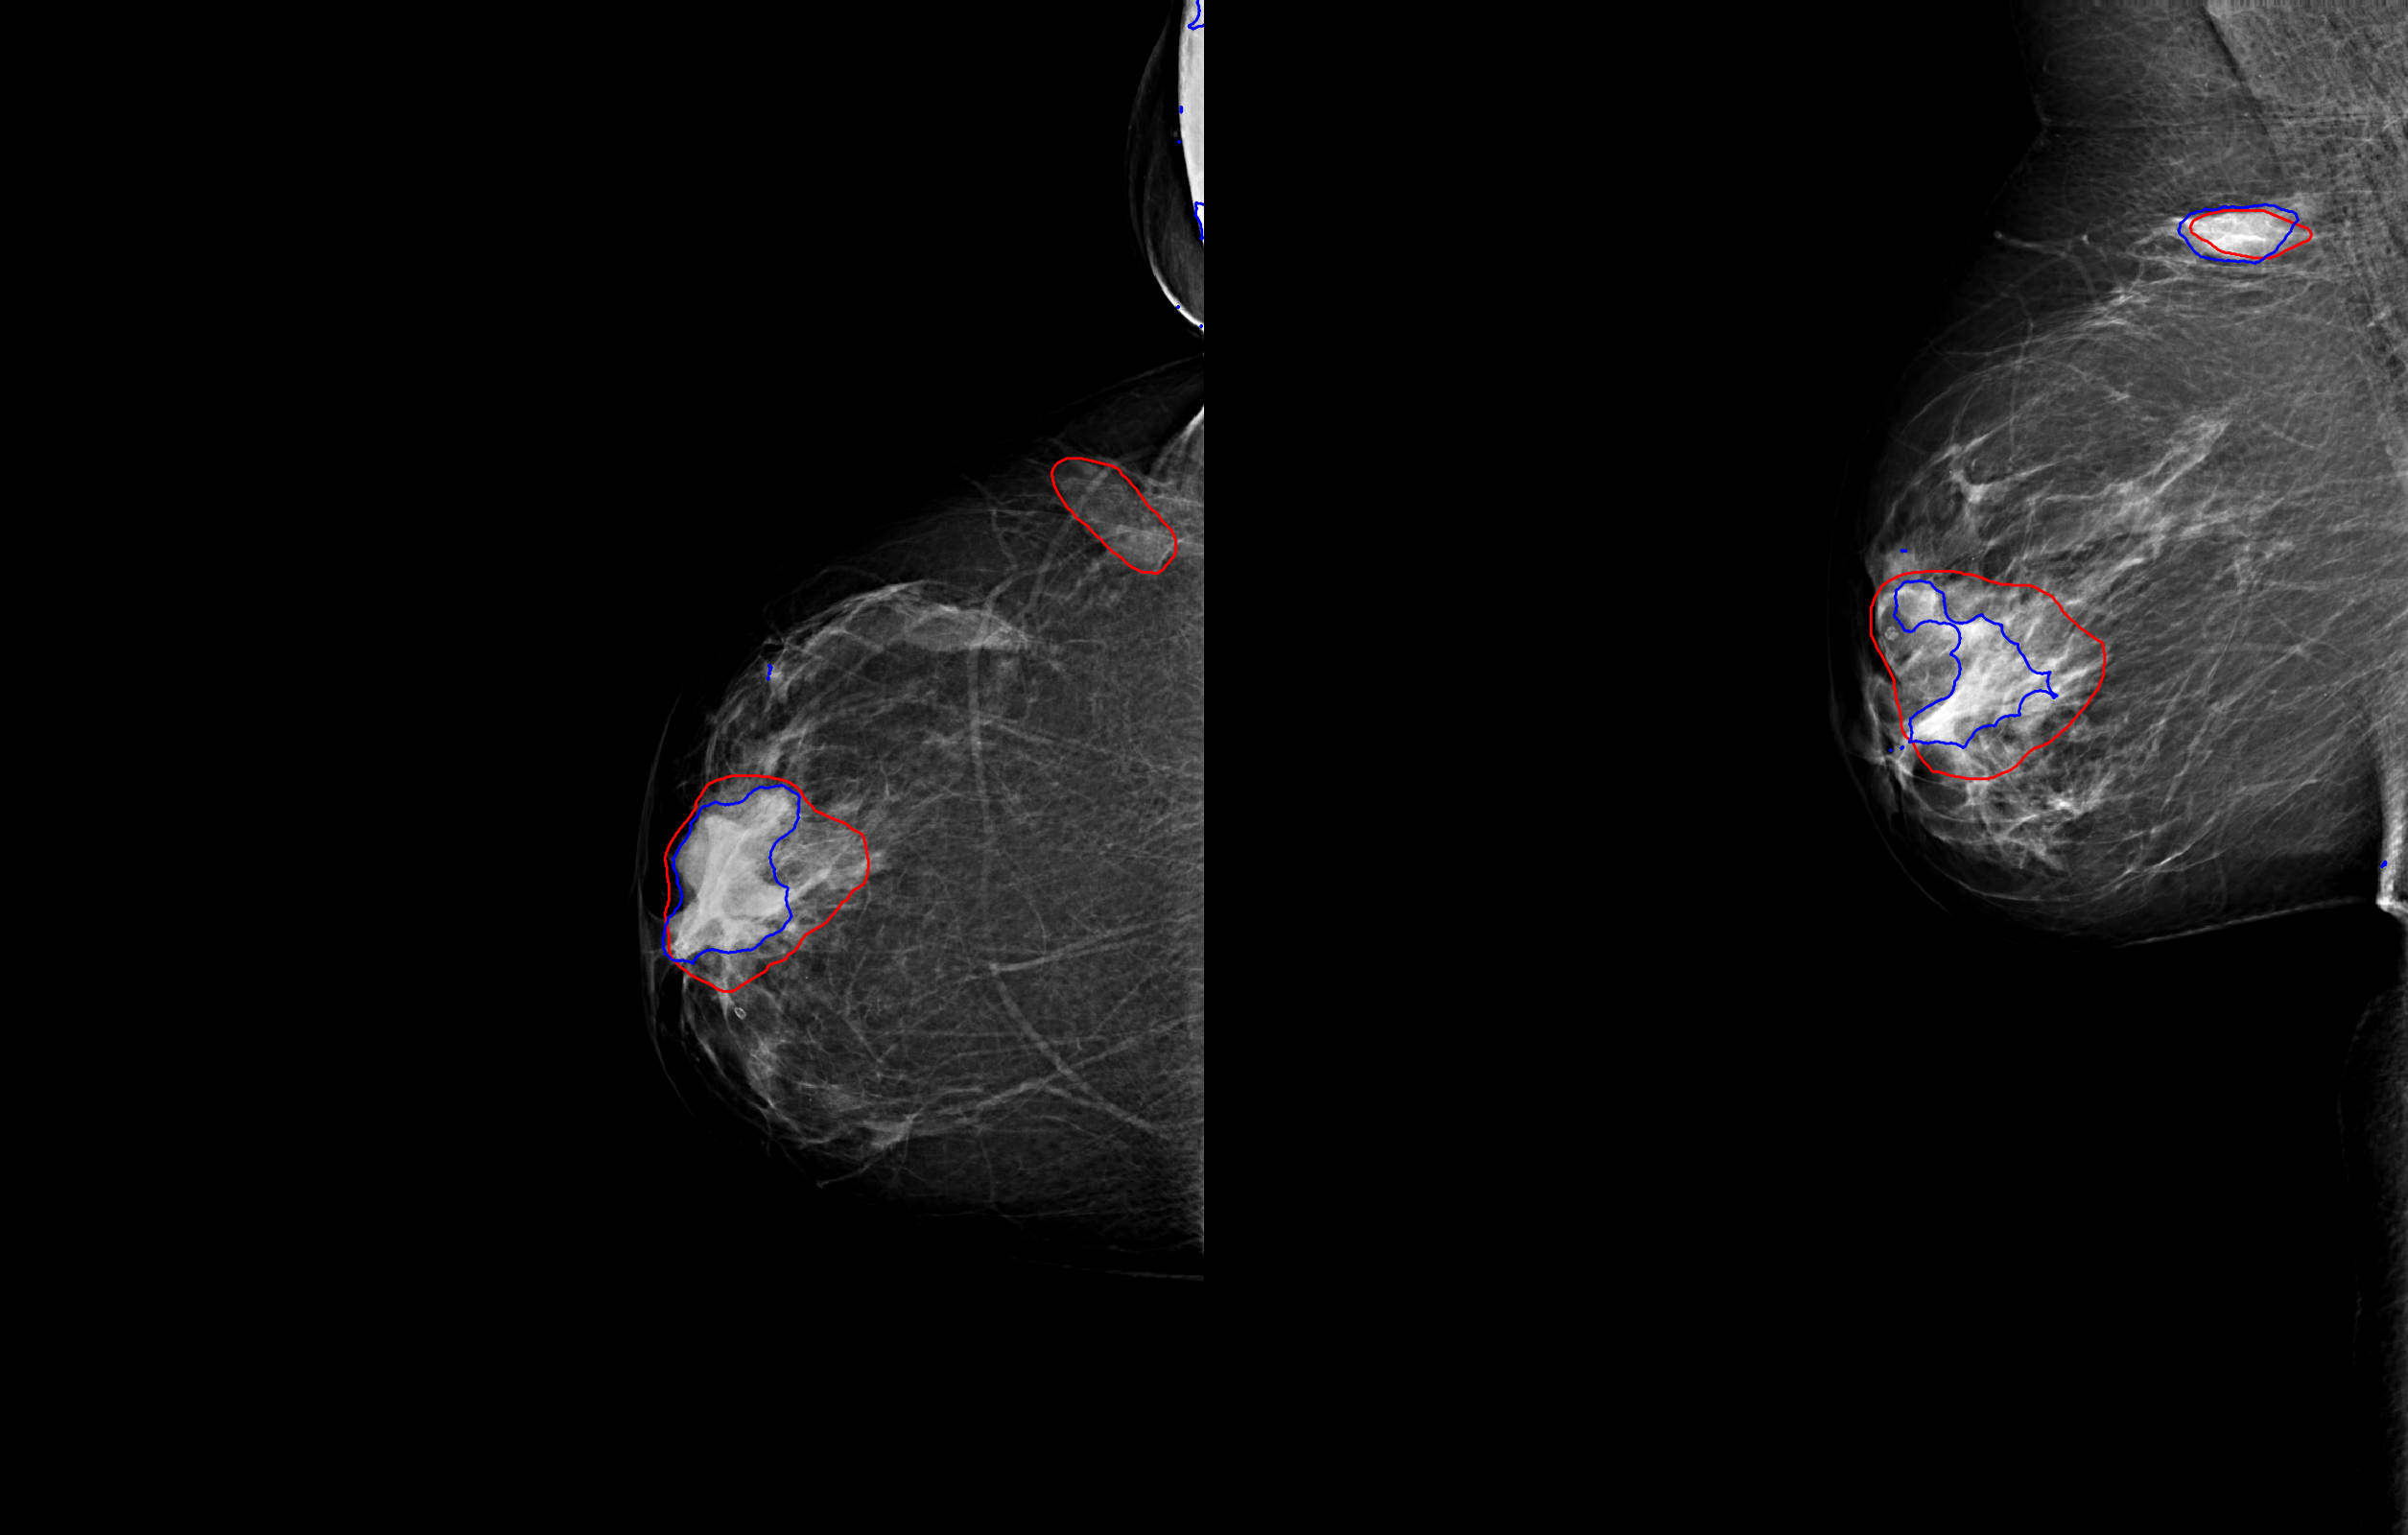

Images were preprocessed in three steps. First, an energy band normalization technique was applied [6]. To homogenize the pixel size across different vendors, images were downscaled to after applying a Gaussian filter. Finally, pixel values were scaled to the range . Examples of preprocessed images with outlined lesions are shown in Figure 1.

All cases with malignant lesions were verified by histopathology and manually annotated and segmented under the supervision of an expert breast radiologist, with access to other breast imaging exams, radiological and histopathological reports. More than of the lesions had a maximal bounding box diameter of and on average had a height/width ratio of about . The negative cases were verified by at least two years of negative follow-up imaging exams.